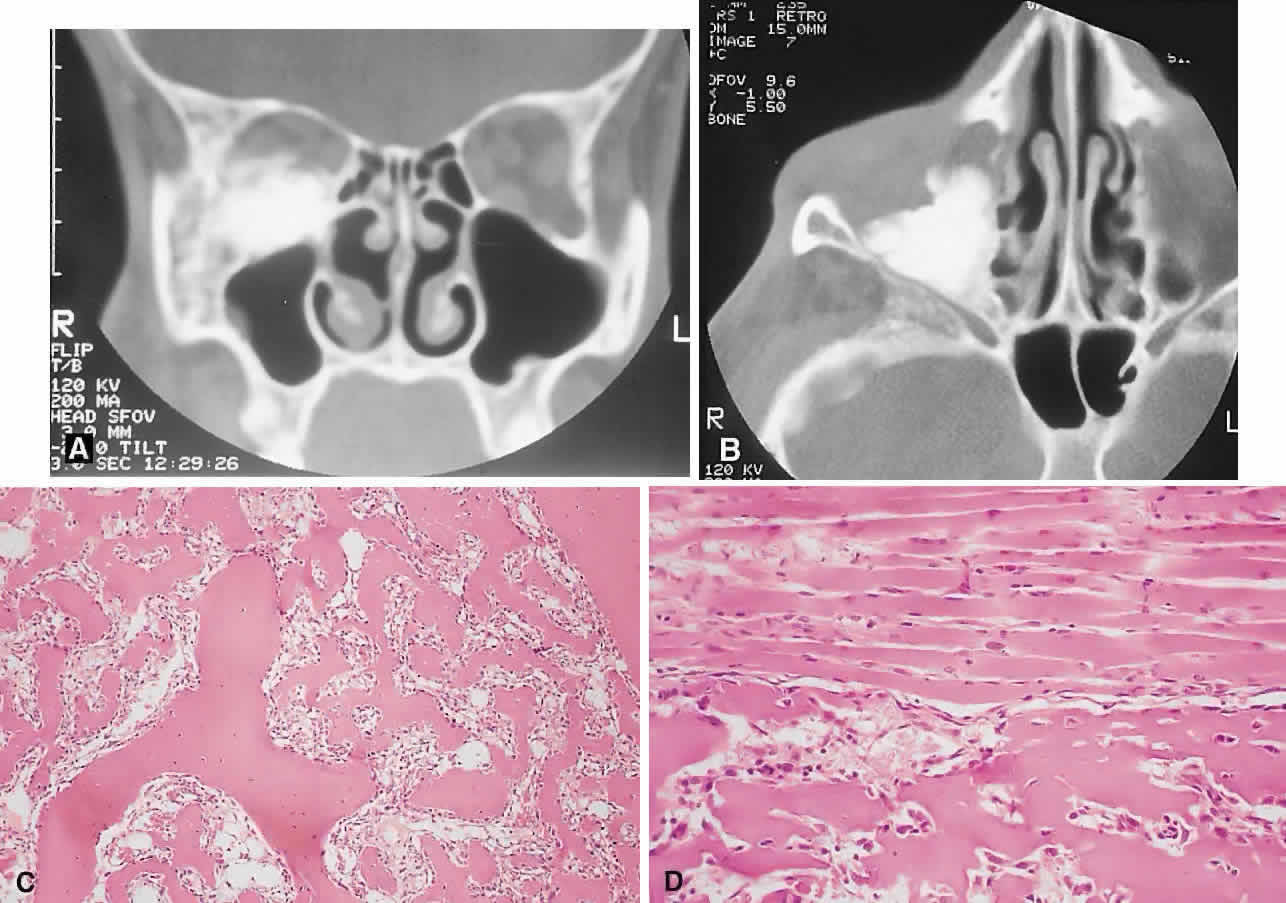

IMAGING. Ossifying fibroma starts as a monostotic lesion that expands the bone of origin in a well-circumscribed manner. However, with growth it may spread to involve adjacent bones and may even extend across the midline to involve both orbits. The characteristic CT appearance is of a round or ovoid mass with a well-defined, thin sclerotic margin (Fig. 3). Centrally, there is often a patchy pattern of osteoblastic and osteolytic areas.46

Fig. 3. A. A 24-year-old man with a 10-year history of increasing right proptosis and a history of ossifying fibroma excised from the right ethmoid and sphenoid 12 years previously. Examination revealed 3 mm of proptosis and 2 mm of lateral globe displacement. B. CT showed a heterogeneous mass with a sclerotic margin involving the right ethmoid and orbit. C and D. After excision, the histology revealed a fibrous stroma containing small spherical ossicles characteristic of the psammomatoid variant of ossifying fibroma (hematoxylin-eosin; C × 20, D × 50). There has been no recurrence in 18 years of follow-up.

HISTOPATHOLOGY. Macroscopically, the lesional tissue is white to red and has a largely soft fibrous texture with variable grittiness, dependent on the amount of osteoid. Microscopically, it consists of a cellular vascular stroma containing trabeculae of lamellar bone. These bony trabeculae often have a thin surrounding of osteoid and, in contrast to fibrous dysplasia, display prominent osteoblastic rimming. There may also be osteoblasts as well as a few foci of giant cells in the stroma. If larger specimens are available, they may demonstrate a zonation phenomenon, seen as an increasing maturity of bone toward the periphery.19

In the psammomatoid variant described by Margo and colleagues,49 at least half of the tumor contains sphericular ossicles. This histologic pattern has been correlated with a more aggressive local behavior and a tendency to recur after incomplete excision.